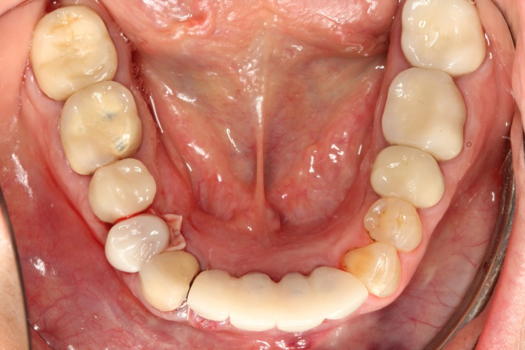

Fig 5. Occlusal view of completed zirconia with porcelain application on teeth Nos. 29, 30, and 31.

Figure 5

After completing an initial diagnostic appointment, a patient accepted three single-unit full-contour zirconia crowns that were milled from the digital impression and cut back for porcelain application. The application by a technician is analog dentistry. The ability of a dental laboratory to scan an analog crown-and-bridge impression is called converting an analog impression to a digital impression. The workflow after the conversion has become digitized. A dental model is virtually created with computer software, and a full crown proposal is fabricated for inspection virtually before the crown is milled (Figure 2). Due to the color of the digitized impression, the margins of the crown preparations are more easily and rapidly identified. The laboratory will also 3D print a working model, which will be used to develop the morphology of the final restoration by hand placement of porcelain (Figure 3). The decision to prescribe a full contour zirconia crown with cutback for porcelain application or complete full contour zirconia crowns lies solely on the attending dentist.9 A discussion with the patient before preparation of the teeth is imperative. After the discussion, the patient requested the zirconia copings with cutback and porcelain application for the posterior crowns (Figure 4 and Figure 5).